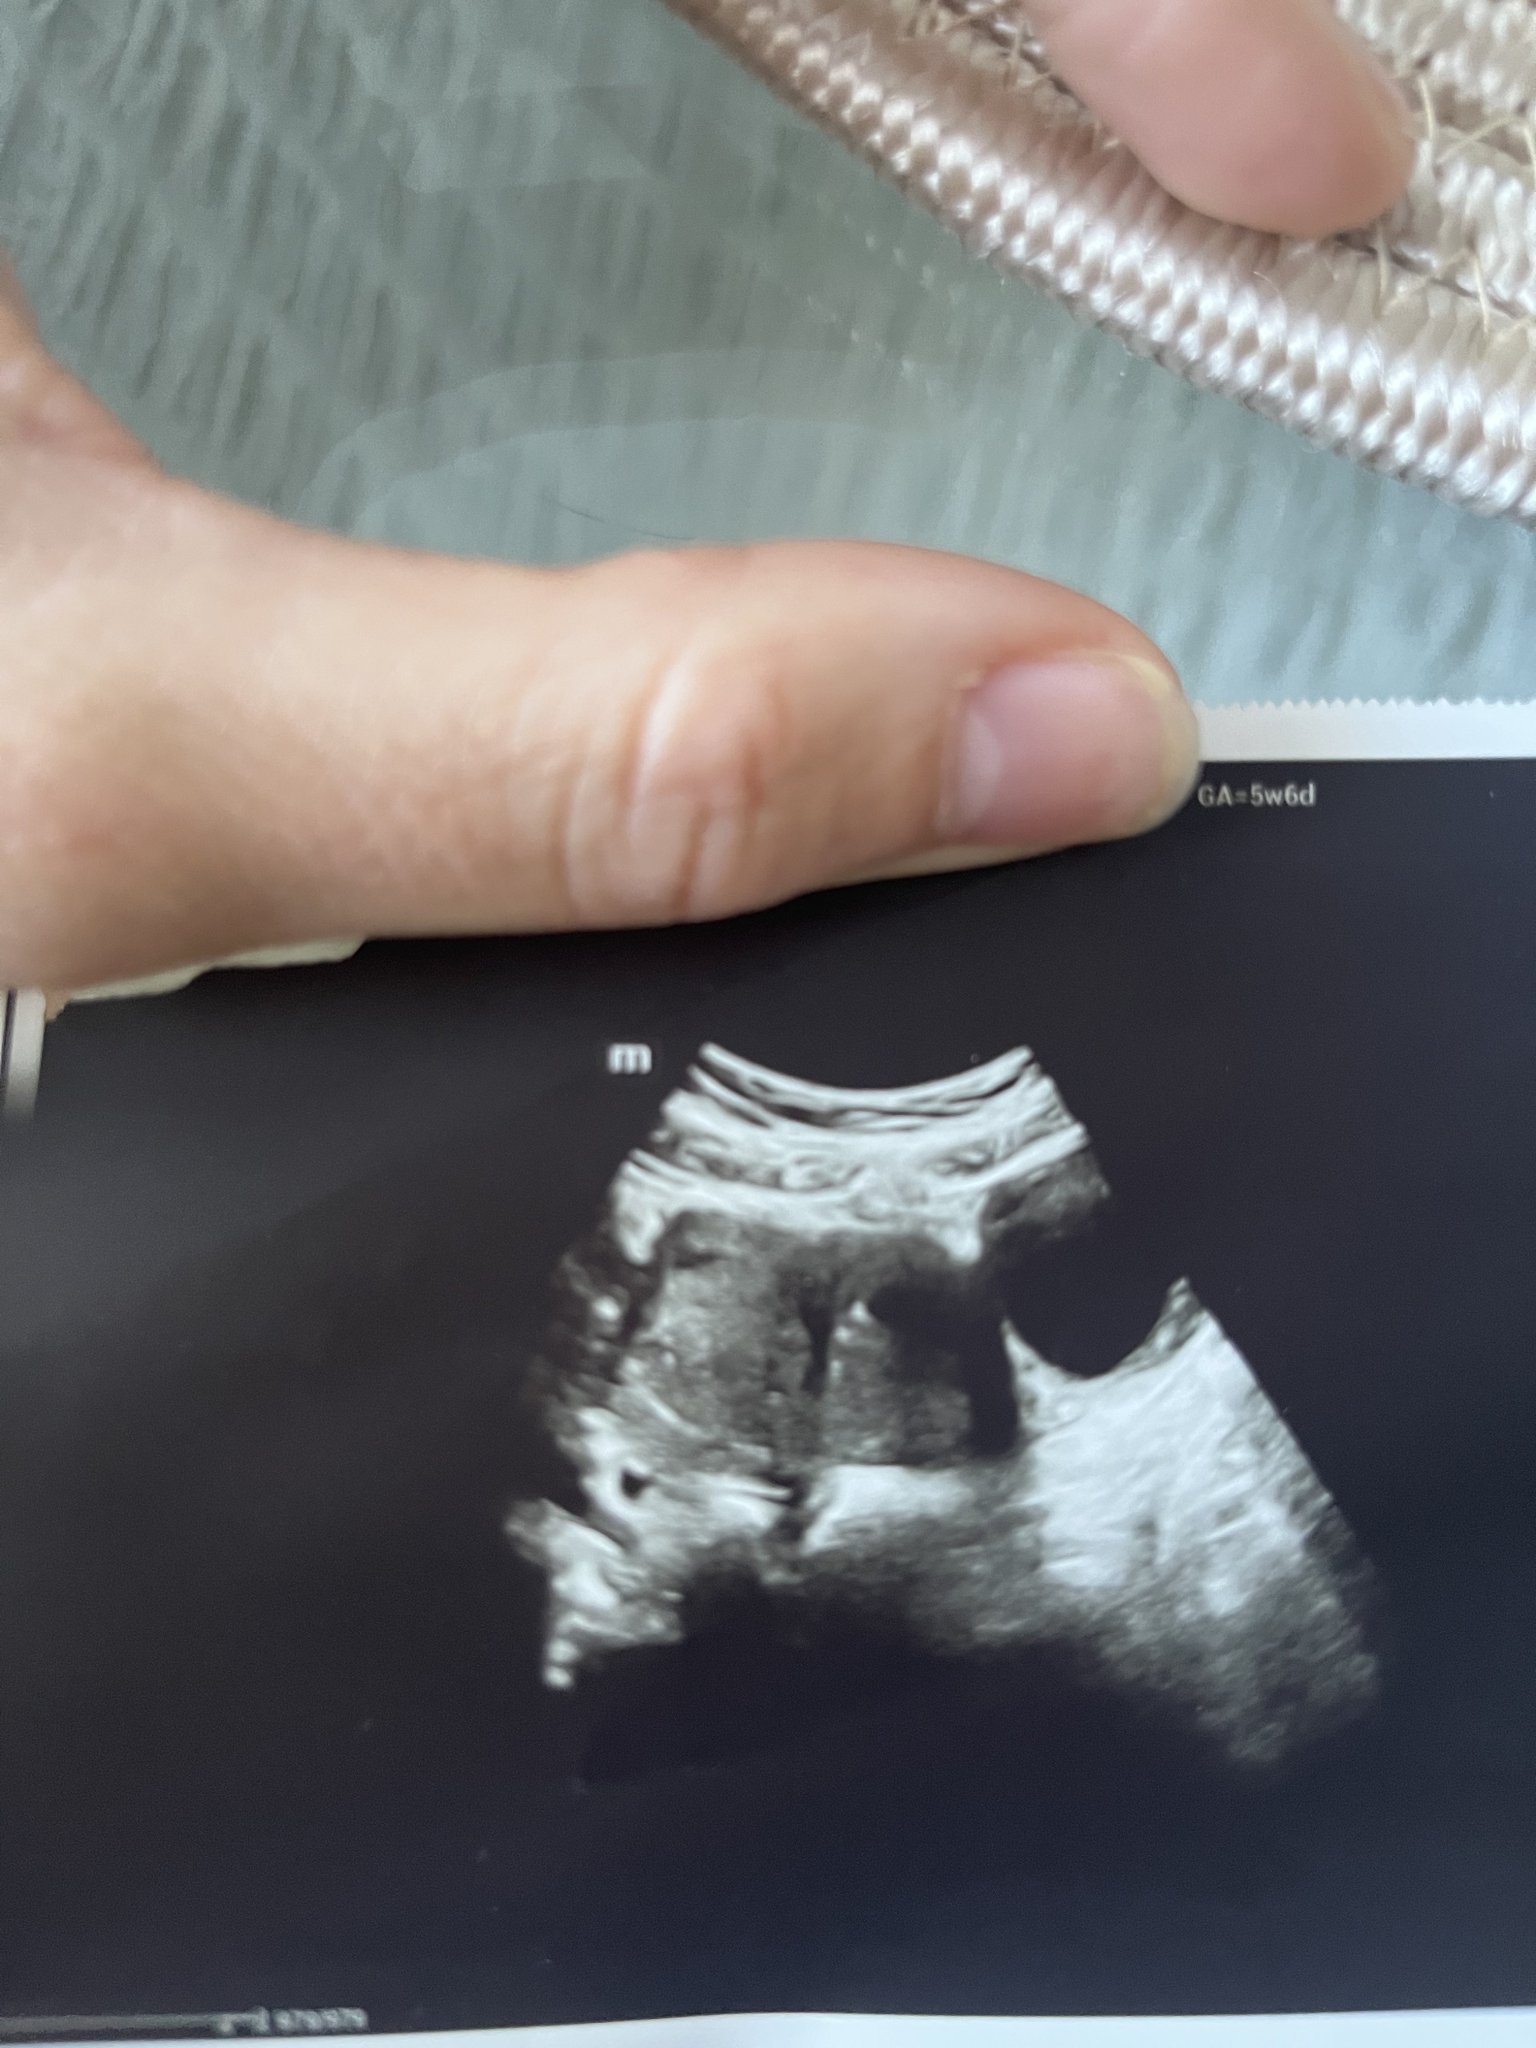

Първия ден на последната ми менструвация беше на 19.09.2023г. 4 положителни теста за бременност. Вччера беше първият ми преглед. Прикачам снимките от него. Видя се плоден сак с размер 18мм, ембрион не. Аз съм с две матки и плодния сак е в лявата матка. В левия яйчник имам и 40мм киста Sad . Притеснено ми е защо при тази големина на плодния сак не се видя ембрион. Преди 8 месеца претърпях куха беменност и се притеснявам изключително много да не се повтори. Чак след месец ще ми бъде следващия преглед, а до тогава ще се побъркам. Моля, ако някой може да помогне със съвет или е бил в подобна ситуация, да пише. Благодаря! Simple Smile

На мен ми изглежда че има нещо в сакчето, не е празно. Ако ще ви успокои, пуснете си чхг  през 48 часа да видите дали се удвоява или отидете още някъде на преглед, да не чакате още месец. Успех!